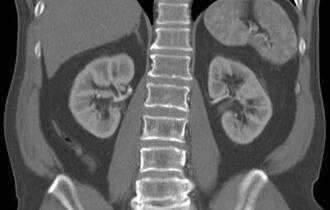

Туберкулез почки

- милиарный туберкулез характеризуется множественными очагами поражения (до 2 мм), локализованными во всех сегментах легких, часто обнаруживают патологии в печени, почках, кишечнике, селезенке, мозге, костях. Данный вид заболевания имеет неблагоприятный прогноз и высокую скорость прогрессии. Поэтому важна ранняя диагностика.

- проблемы с печенью или почками. Печень и почки помогают фильтровать отходы и примеси из кровотока. Туберкулез этих органов может нарушать их функции